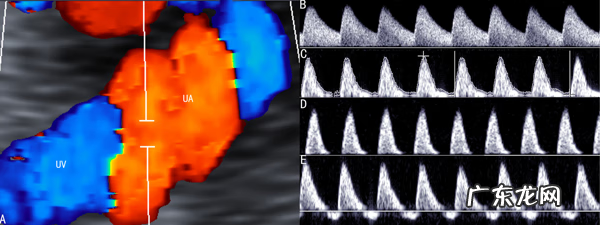

彩超是超声显像诊断法和多普勒型超声诊断法结合的超声检查技术 。

反应运动器官或血液反射声波频率变化超声检查技术称为D(Doppler)型超声诊断法 。超声波在人体内遇到流动的血液时,反射声波的频率将和原谅声波频率不同:如果血流迎着声波流动,反射声波频率会增加,反之则降低 。流动的速度越快,变化的程度越大 。这种现象称为多普勒效应 。D型超声诊断法就是利用了移动的物体多普勒效应诊断疾病的方法 。一般情况下,我们以红色显示频率增加的反射声波,也就是迎着声波流动的血液产生的回声,以蓝色显示频率降低的声波,也就是背离声波流动的血液产生的回声 。将翻译血流的色彩与显示的人体器官解剖图像重叠显示,就形成了既能显示人体器官结构、又可以显示相应部位的血液移动信息的彩色多普勒显像,超声显像技术和超声多普勒技术完美地结合,简称彩超 。

由此可知,显示的血流色彩并不是人们一般理解的动脉或静脉,而是反应了不同流动方向的血流 。

彩色多普勒血流成像系统不仅可以获取血细胞移动信息,而且二维图像质量也有很大的提高,器官影像更加清晰,分辨率更高,使人们能无创伤地观察心脏及大血管的大小、形态、内部结构、运动状况,以及在正常和病理状态下的血流动力学状态,扩大了超声检查的应用范围 。目前,彩超除用于心脏和大血管的检查外,对肝脏、肾脏以及浅表器官的血流评价,对移植器官的评价和占位性病变的检查都有重要的意义 。